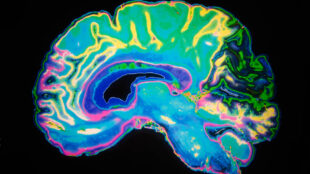

Blodflödet i hjärnan kan visa på bäst behandling

Stört blodflöde förekommer vid många sjukdomar. Nu kan blodflödet i hjärnan analyseras automatiskt med ny kraftfull...